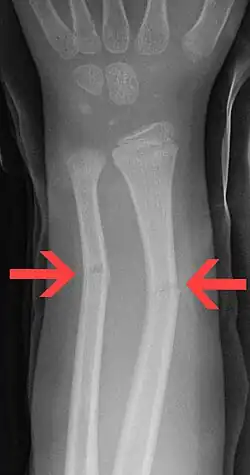

Fractura en tallo verde

En medicina, se denomina fractura en tallo verde a un tipo de fractura ósea propia de los niños. Afecta a la región central (diáfisis) de los huesos largos, sobre todo en el antebrazo. La denominación en tallo verde procede de la analogía entre este tipo de fractura y la que se produce al intentar romper el tallo verde de una planta.

Se caracteriza por ser una fractura incompleta, con ruptura del periostio y la cortical en el lado de la convexidad del hueso, mientras que en la zona cóncava el periostio no llega a romperse, como consecuencia el hueso no está totalmente roto (fractura incompleta), pero los fragmentos se desplazan y presentan una angulación de amplitud variable que es preciso corregir. [1][2]

Las fracturas en tallo verde afectan por lo general a la porción central o diáfisis de los huesos largos de los niños, sobre todo a la región del antebrazo, muñeca y clavícula. Raramente se produce en otros huesos como la tibia y el fémur. Cuando afecta al antebrazo puede existir fractura del cúbito, el radio o ambos huesos simultáneamente.